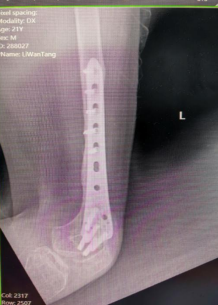

左股骨延长术后患者情况

在Ilizarov外固定支架的保护下,患者的运动功能被完好地进行了保留,且左腿每天都在加速“生长”。通过几个月的康复训练后,李先生再次到医院进行左股骨延长术后钢板内固定+拆除外固定支架术。术后唐继全查看患者左腿肢恢复情况,并叮嘱他一定要做好术后康复锻炼,早日恢复肌体功能。

Ilizarov骨延长手术中医师需要在左股骨截骨延长单边轨道外安装一个固定支架,就像盖房子的脚手架一样,通过钢针将外固定架和病损骨骼连为一体,医生会在骨骼上做适当的截骨,再慢慢延长使骨骼延伸生长。